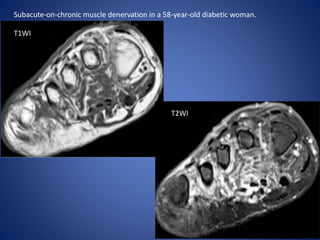

Subacute-on-chronic muscle denervation in a 58-year-old diabetic woman.

T1WI

T2WI

Subacute-on-chronic muscle denervationin a 58-year-old diabetic woman. T1WI T2WI

• #18 Short-axis T1-weighted (a) and T2-weighted fat-suppressed (b) MR images of the right forefoot demonstrate mild fatty infiltration of the intrinsic musculature.